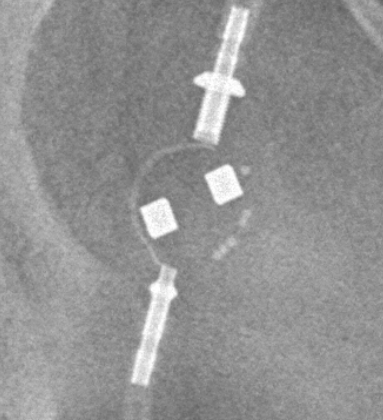

Medtronic Strata NSC

Medtronic Strata NSC valves are adjustable csf shunt valves.